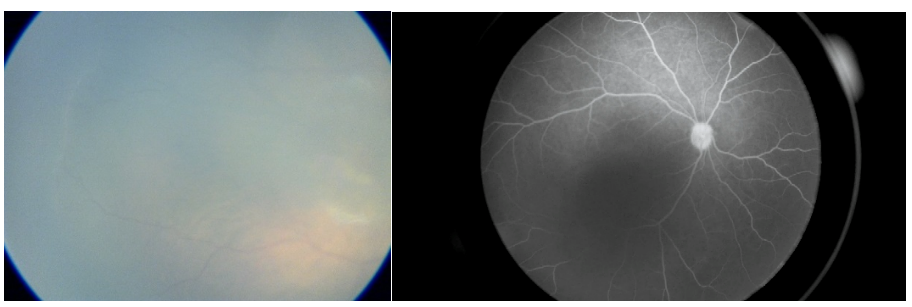

男童,3岁,发现左眼外斜1个月。眼底检查发现颞侧下方视网膜脱离伴后极部视网膜下脂质沉着,B超示视网膜球形隆起,属于Coats病3A期,采用光凝联合抗VEGF治疗方案。本例考虑到异常血管病灶相对局限且靠近周边,其下积液不多,尝试了2次眼外光凝治疗未做巩膜外放液,随访观察中视网膜脱离高度和范围均有减少,但5个月后仍有视网膜下液,病情尚未完全控制,再次行巩膜外放液后眼内光凝联合抗VEGF治疗,7个月后视网膜下液完全吸收,随访至今已超过3年,病情稳定,VOS 0.4,未观察到纤维化。

术前检查

3次激光术后7个月